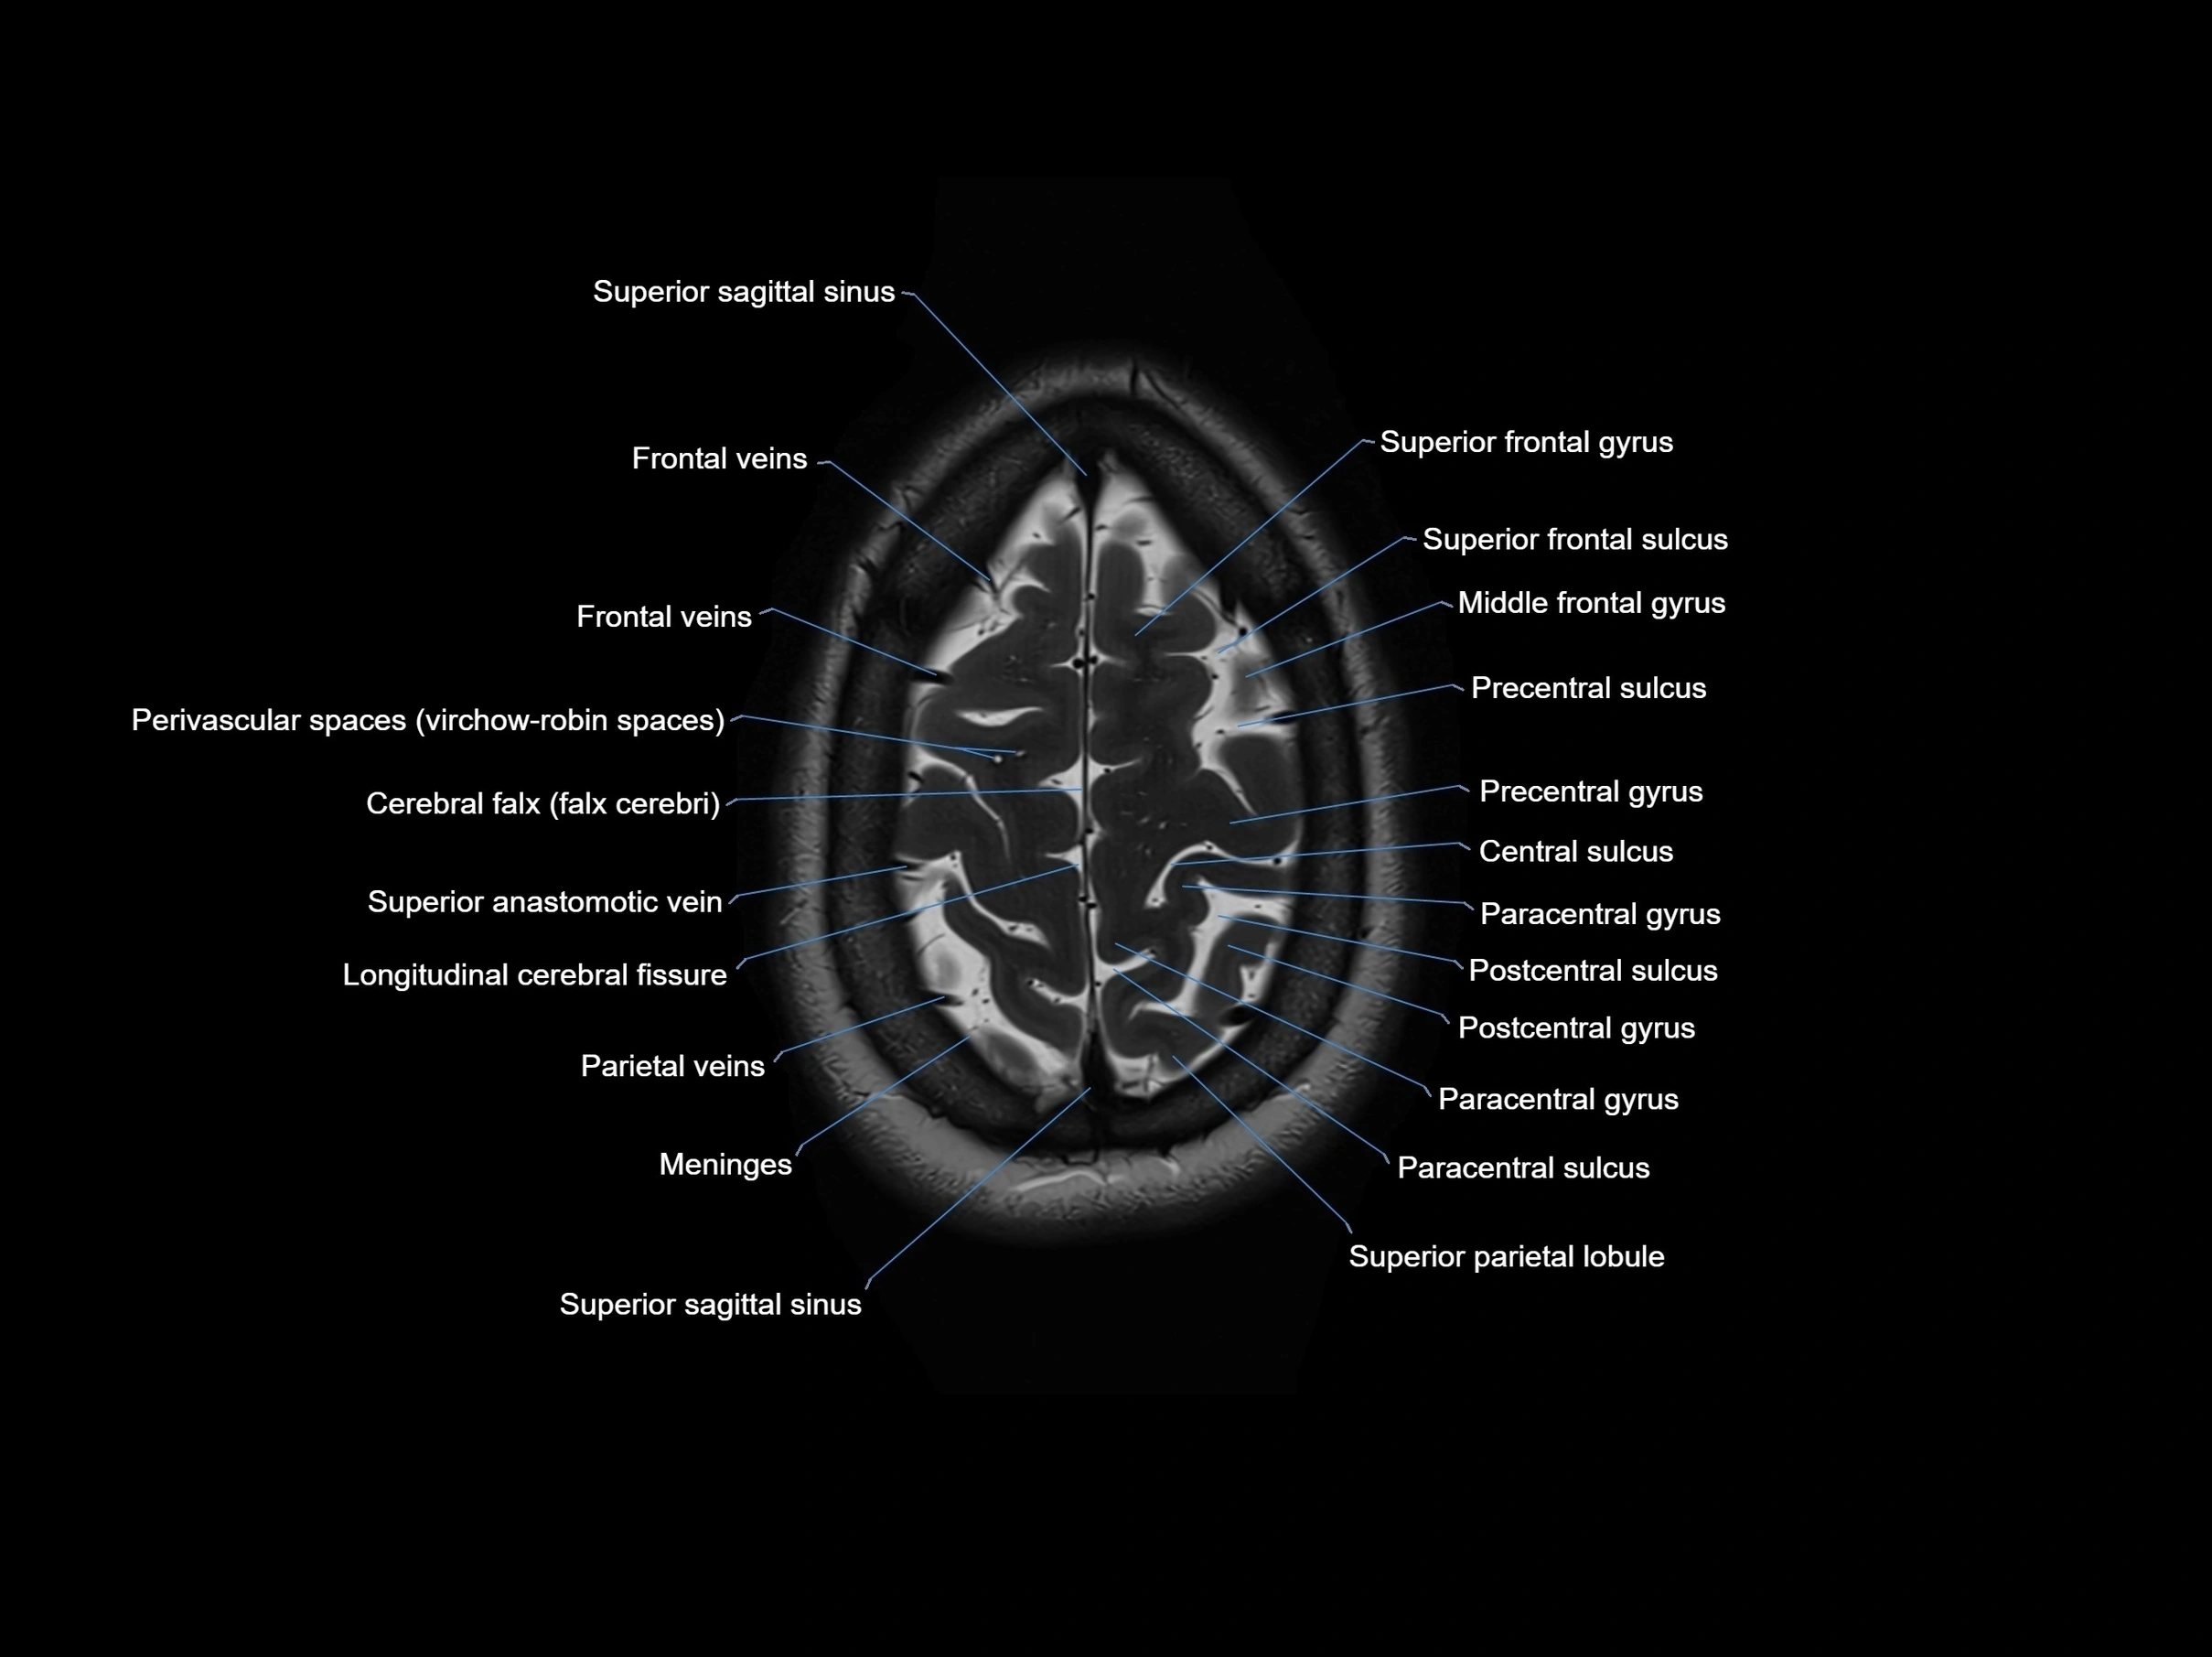

- Central sulcus

- Cerebral falx

- Frontal veins

- Longitudinal cerebral fissure

- Meninges

- Paracentral gyrus

- Paracentral sulcus

- Parietal veins

- Perivascular spaces

- Postcentral gyrus

- Postcentral sulcus

- Precentral gyrus

- Precentral sulcus

- Superior anastomotic vein

- Superior frontal gyrus

- Superior frontal sulcus

- Superior occipital gyrus

- Superior parietal lobule

- Superior sagittal sinus